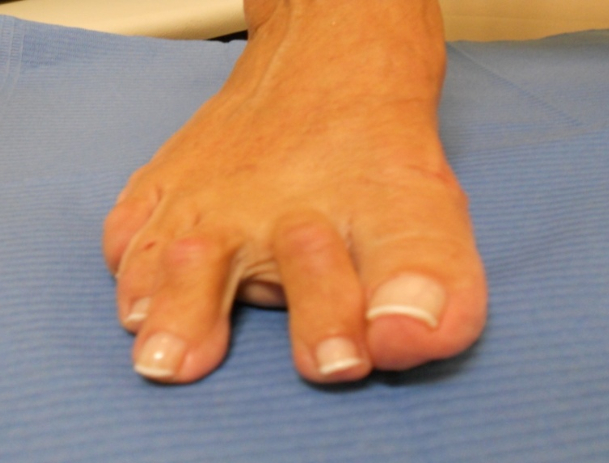

Hallux valgus (juanete) y dedos en garra

Hallux valgus (juanete) y dedos en garra: antes Hallux valgus (juanete) y dedos en garra: después

Hallux Valgus (juanete)

Hallux valgus: antes Hallux valgus: después